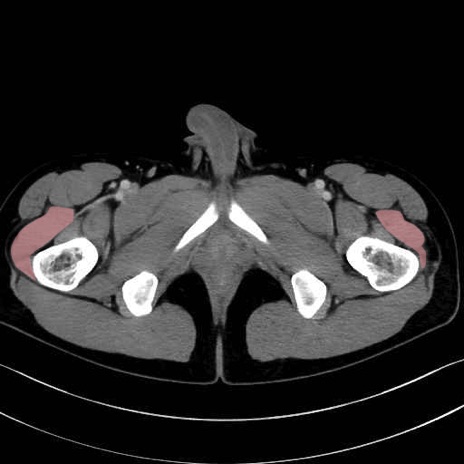

外側広筋 (Vastus lateralis)